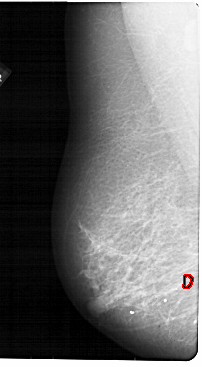

A_1868_1.LEFT_CC

LEFT_CC LINES 5491 PIXELS_PER_LINE 2776 BITS_PER_PIXEL 12 RESOLUTION 43.5 OVERLAY

FILE: A_1868_1.LEFT_CC.OVERLAY

TOTAL_ABNORMALITIES 1

ABNORMALITY 1

LESION_TYPE CALCIFICATION TYPE PLEOMORPHIC DISTRIBUTION CLUSTERED

ASSESSMENT 4

SUBTLETY 3

PATHOLOGY BENIGN

TOTAL_OUTLINES 1